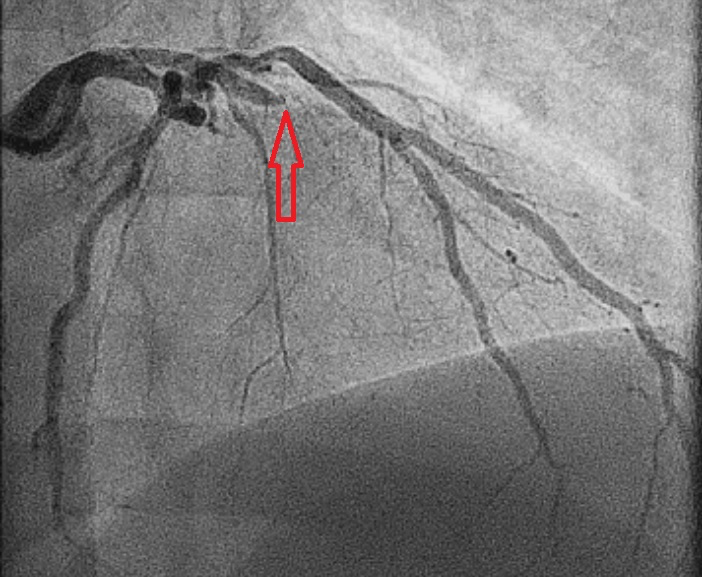

Figuur 2: Met de rode pijl is aangegeven waar de occlusie zich bevindt.